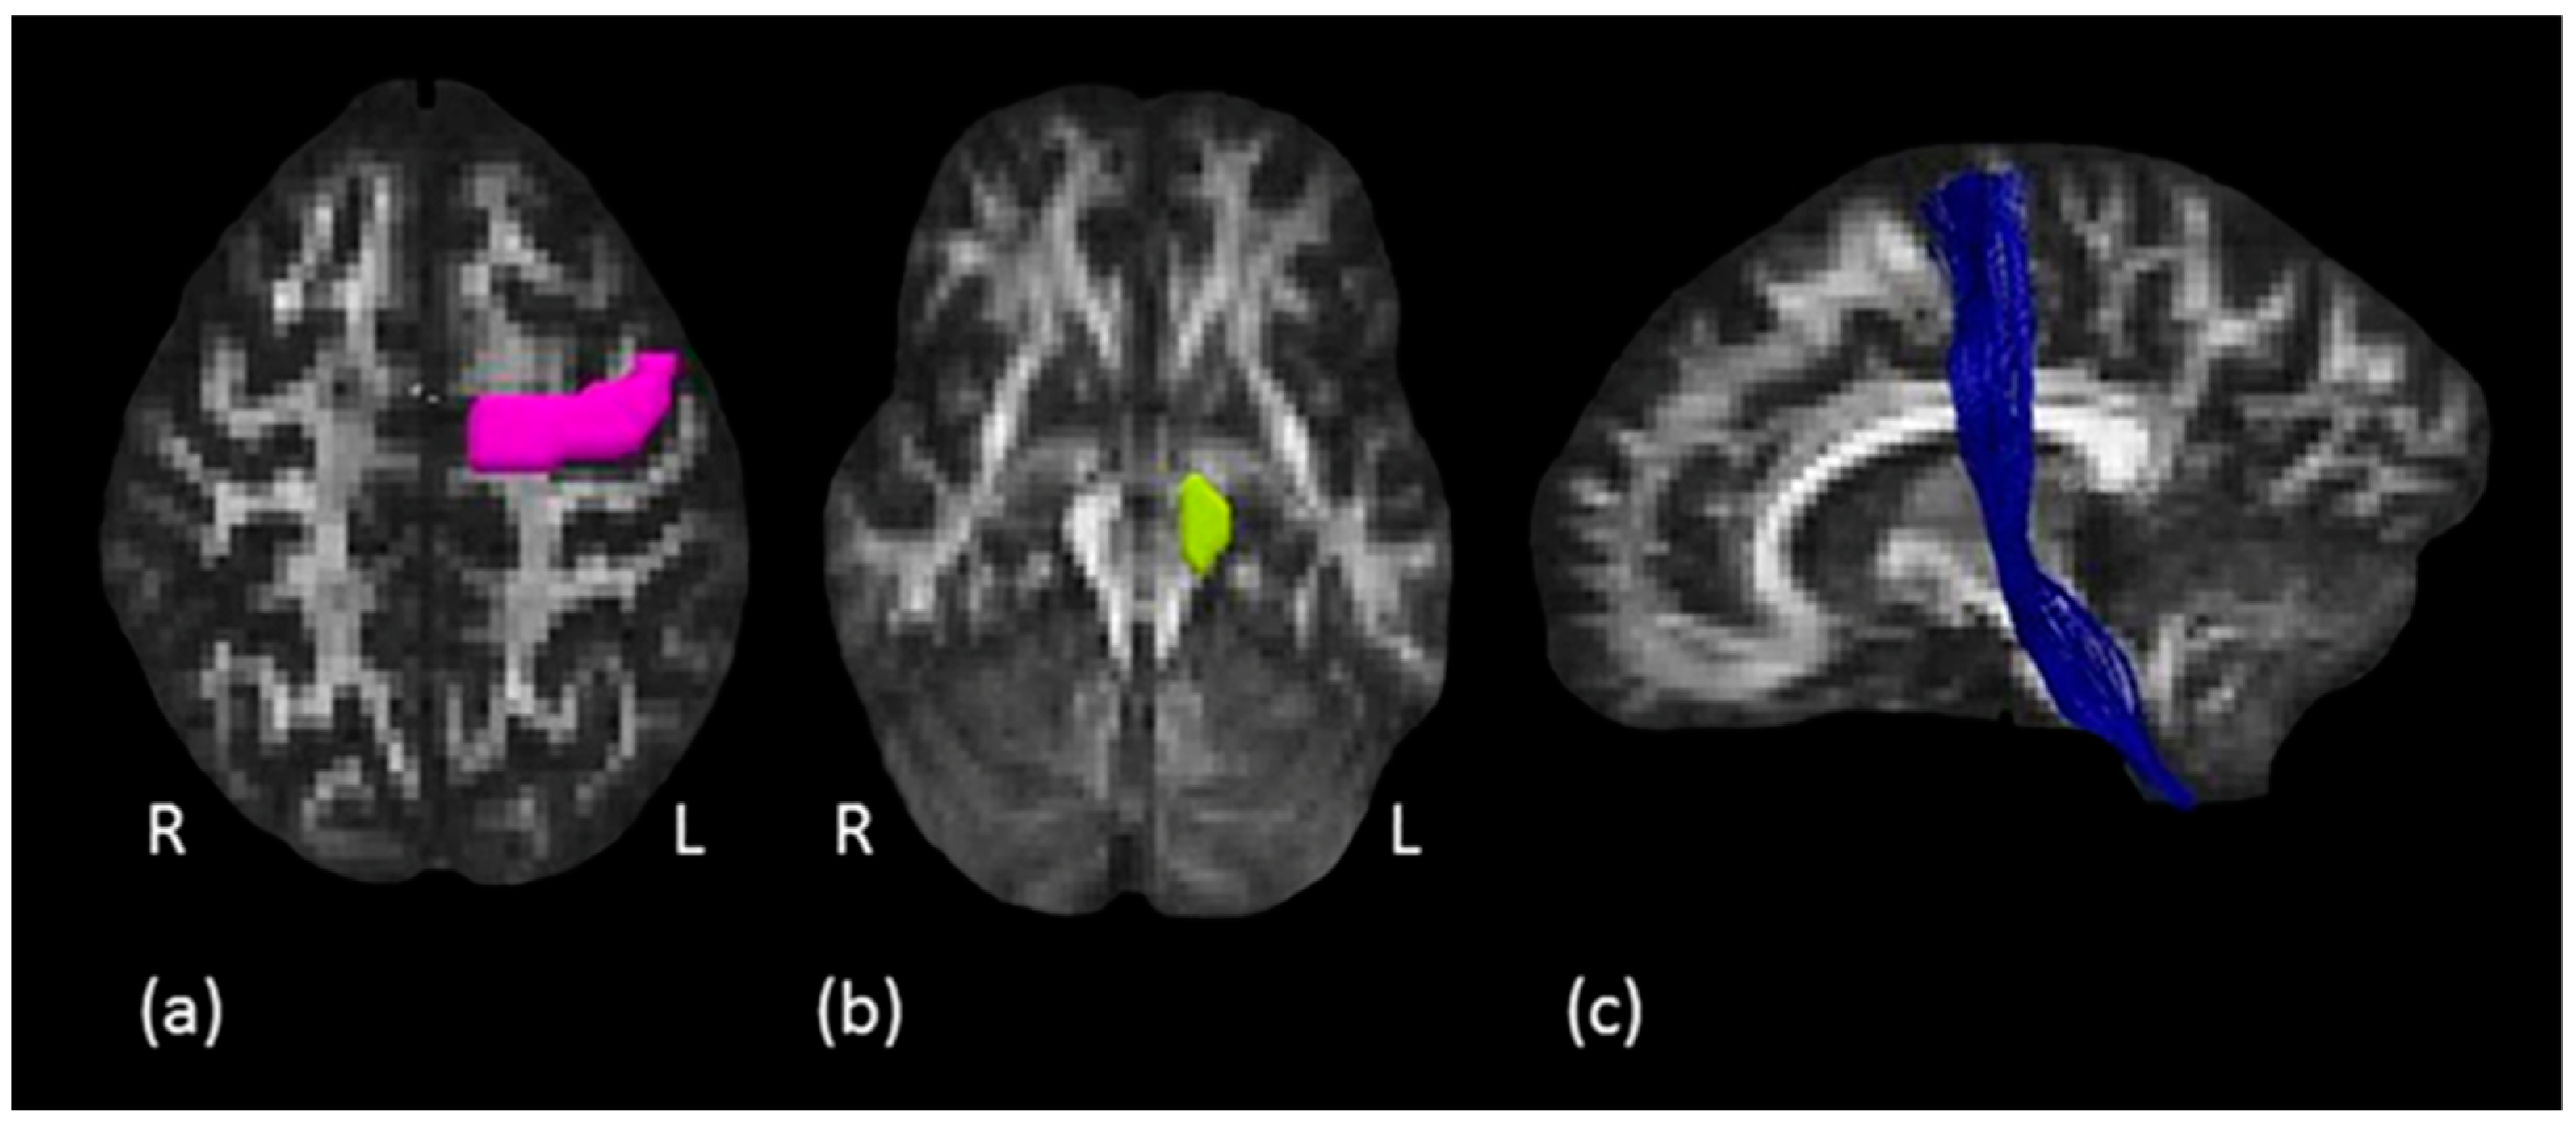

2.3.4. Tractography Dissections of the Internal Capsule, Corticospinal Tract and Hand Motor Tract